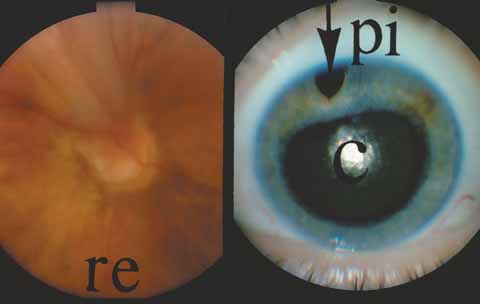

Schwartz Syndrome (Rod Outer Segment Obstruction)

In 1973, Schwartz described 11 patients with a unilateral elevation of intraocular pressure, ranging from 29 to 55 mm Hg, who were found to have a rhegmatogenous retinal detachment that in some cases had been overlooked previously.33 Schwartz found the angles were open and normal except for one patient with an angle recession (5 of 11 patients had a history of trauma). The elevated pressures responded poorly to glaucoma medications given prior to the correct diagnosis, and successful retinal repair resulted in a normal intraocular pressure and outflow facility. More recent work34,35 suggests that trabecular obstruction by photoreceptor outer segments may play a role, although reduced aqueous outflow due to pigment dispersion and trabecular damage from previous trauma are all possible mechanisms of the glaucoma in this syndrome. This unique entity should be differentiated from coexistent primary open-angle glaucoma, which is usually bilateral, and from uveitic glaucoma, which generally responds to corticosteroids. It is important to exclude an occult retinal detachment in any medically unresponsive unilateral glaucoma especially prior to instituting miotics. Chronic miotic instillation may impair pupil size and compromise future retinal evaluation.

Silicone Oil/Gas

Over the past two decades silicone oil (dimethylpolysiloxane) has enjoyed a resurgence in the repair of complicated retinal detachments. In 1967, Watzke36 found no pressure elevation attributable to silicone but described droplets in the superior angle that result from silicone's lower specific gravity (buoyancy) compared with water. Silicone-induced glaucoma does occur, however, and one possible mechanism is an acute pupillary block due to the buoyancy of the silicone sometimes combined with overfilling the aphakic eye (Fig. 5). This can be averted by performing an inferior iridectomy and by paying careful attention to the silicone volume injected. A second mechanism involves chronic obstruction of an open angle by emulsified silicone microbubbles (more likely with low viscosity silicone, 1,000 centistokes, than high viscosity silicone, 12,500 centistokes) (Fig. 6), pigmented cells, and silicone-laden macrophages or silicone-induced fibrosis of the trabecular meshwork due to possible inherent fibrogenicity of this compound.37,38 Treatment of this open-angle glaucoma is generally medical, although silicone removal may be required. Although some studies have confirmed the presence of emulsified oil in the anterior chamber as a strong predictor of pressure elevation, others do not, suggesting that multiple factors are at play.39,40,41,42 Often this can only be seen on gonioscopy, and removal of the oil, if possible, is beneficial in some cases. Sometimes an expected pressure elevation that would otherwise occur may be muted by concomitant cyclitic membrane formation or hypotony associated with recurrent retinal detachment. The use of shunt procedures in this difficult glaucoma has led to the unusual complication of silicone oil escape into the subconjunctival space43,44 (Fig. 7). Whether placed superiorly or inferiorly, shunts should probably be avoided in these eyes unless the silicone oil can first be safely removed. Transscleral diode laser cyclophotocoagulation has been proven to be an excellent noninvasive option in treating these eyes for recalcitrant pressure elevation.45,46